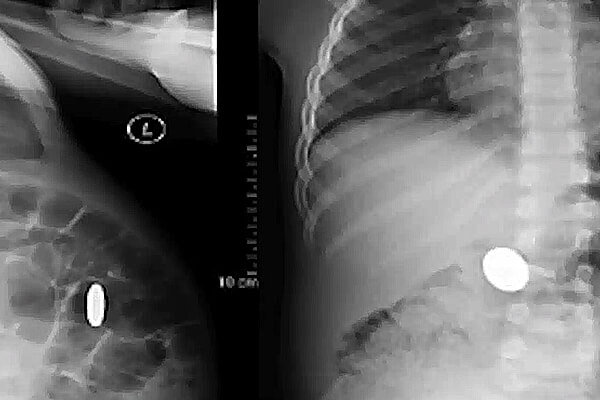

Removal of Accidently Swallowed Items